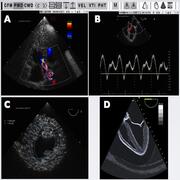

Our lab is one of the largest echocardiography simulation centers in the world. Our residents and fellows have access to 8 state-of-the-art simulators that can be used for training in transthoracic echocardiography, transesophageal echocardiography, focused assessment with sonography for trauma (FAST) examination, ultrasound knobology, hemodynamics, and lung ultrasound. Our simulators also have a wide range of pathologies and the possibility of evaluating trainee progress with motion analysis.